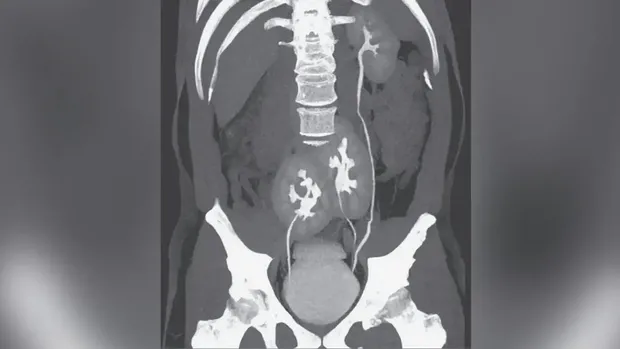

Untuk menelusuri sumber keluhan, dokter melakukan serangkaian pemeriksaan, termasuk CT scan. Hasilnya menunjukkan bahwa pasien memiliki tiga ginjal. Selain satu ginjal kiri dengan bentuk normal, ia juga memiliki dua ginjal lain yang menyatu dan berada di area panggul.

pria punya 3 ginjalpria punya 3 ginjal Foto: The New England Journal of Medicine (NEJM).

Dalam laporan, tim dokter juga menjelaskan jalur saluran kencing pasien. Ureter dari ginjal panggul kiri bergabung dengan ureter dari ginjal kiri normal sebelum masuk ke kandung kemih, sementara ureter dari ginjal panggul kanan masuk langsung ke kandung kemih di sisi kanan. Meski bentuknya tidak biasa, fungsi seluruh ginjal pasien tercatat normal.